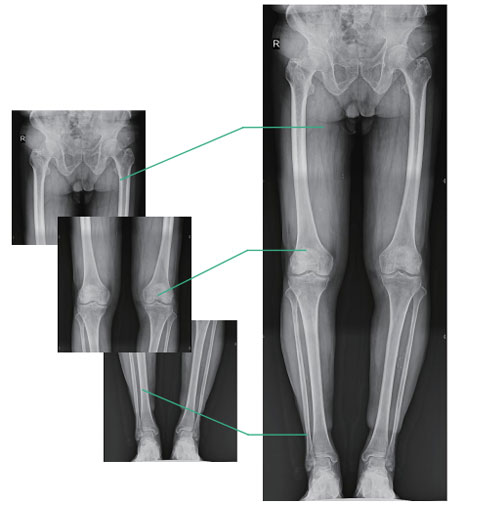

● One standard dynamic detector for full stitching functionality.

● Highly practical, low maintenance and cost saving for hospitals.

● Panoramic stitching of full lower limb or full spine images.

● A reliable basis for preoperative planning and postoperative review in the treatment of spinal and lower limb deformities.